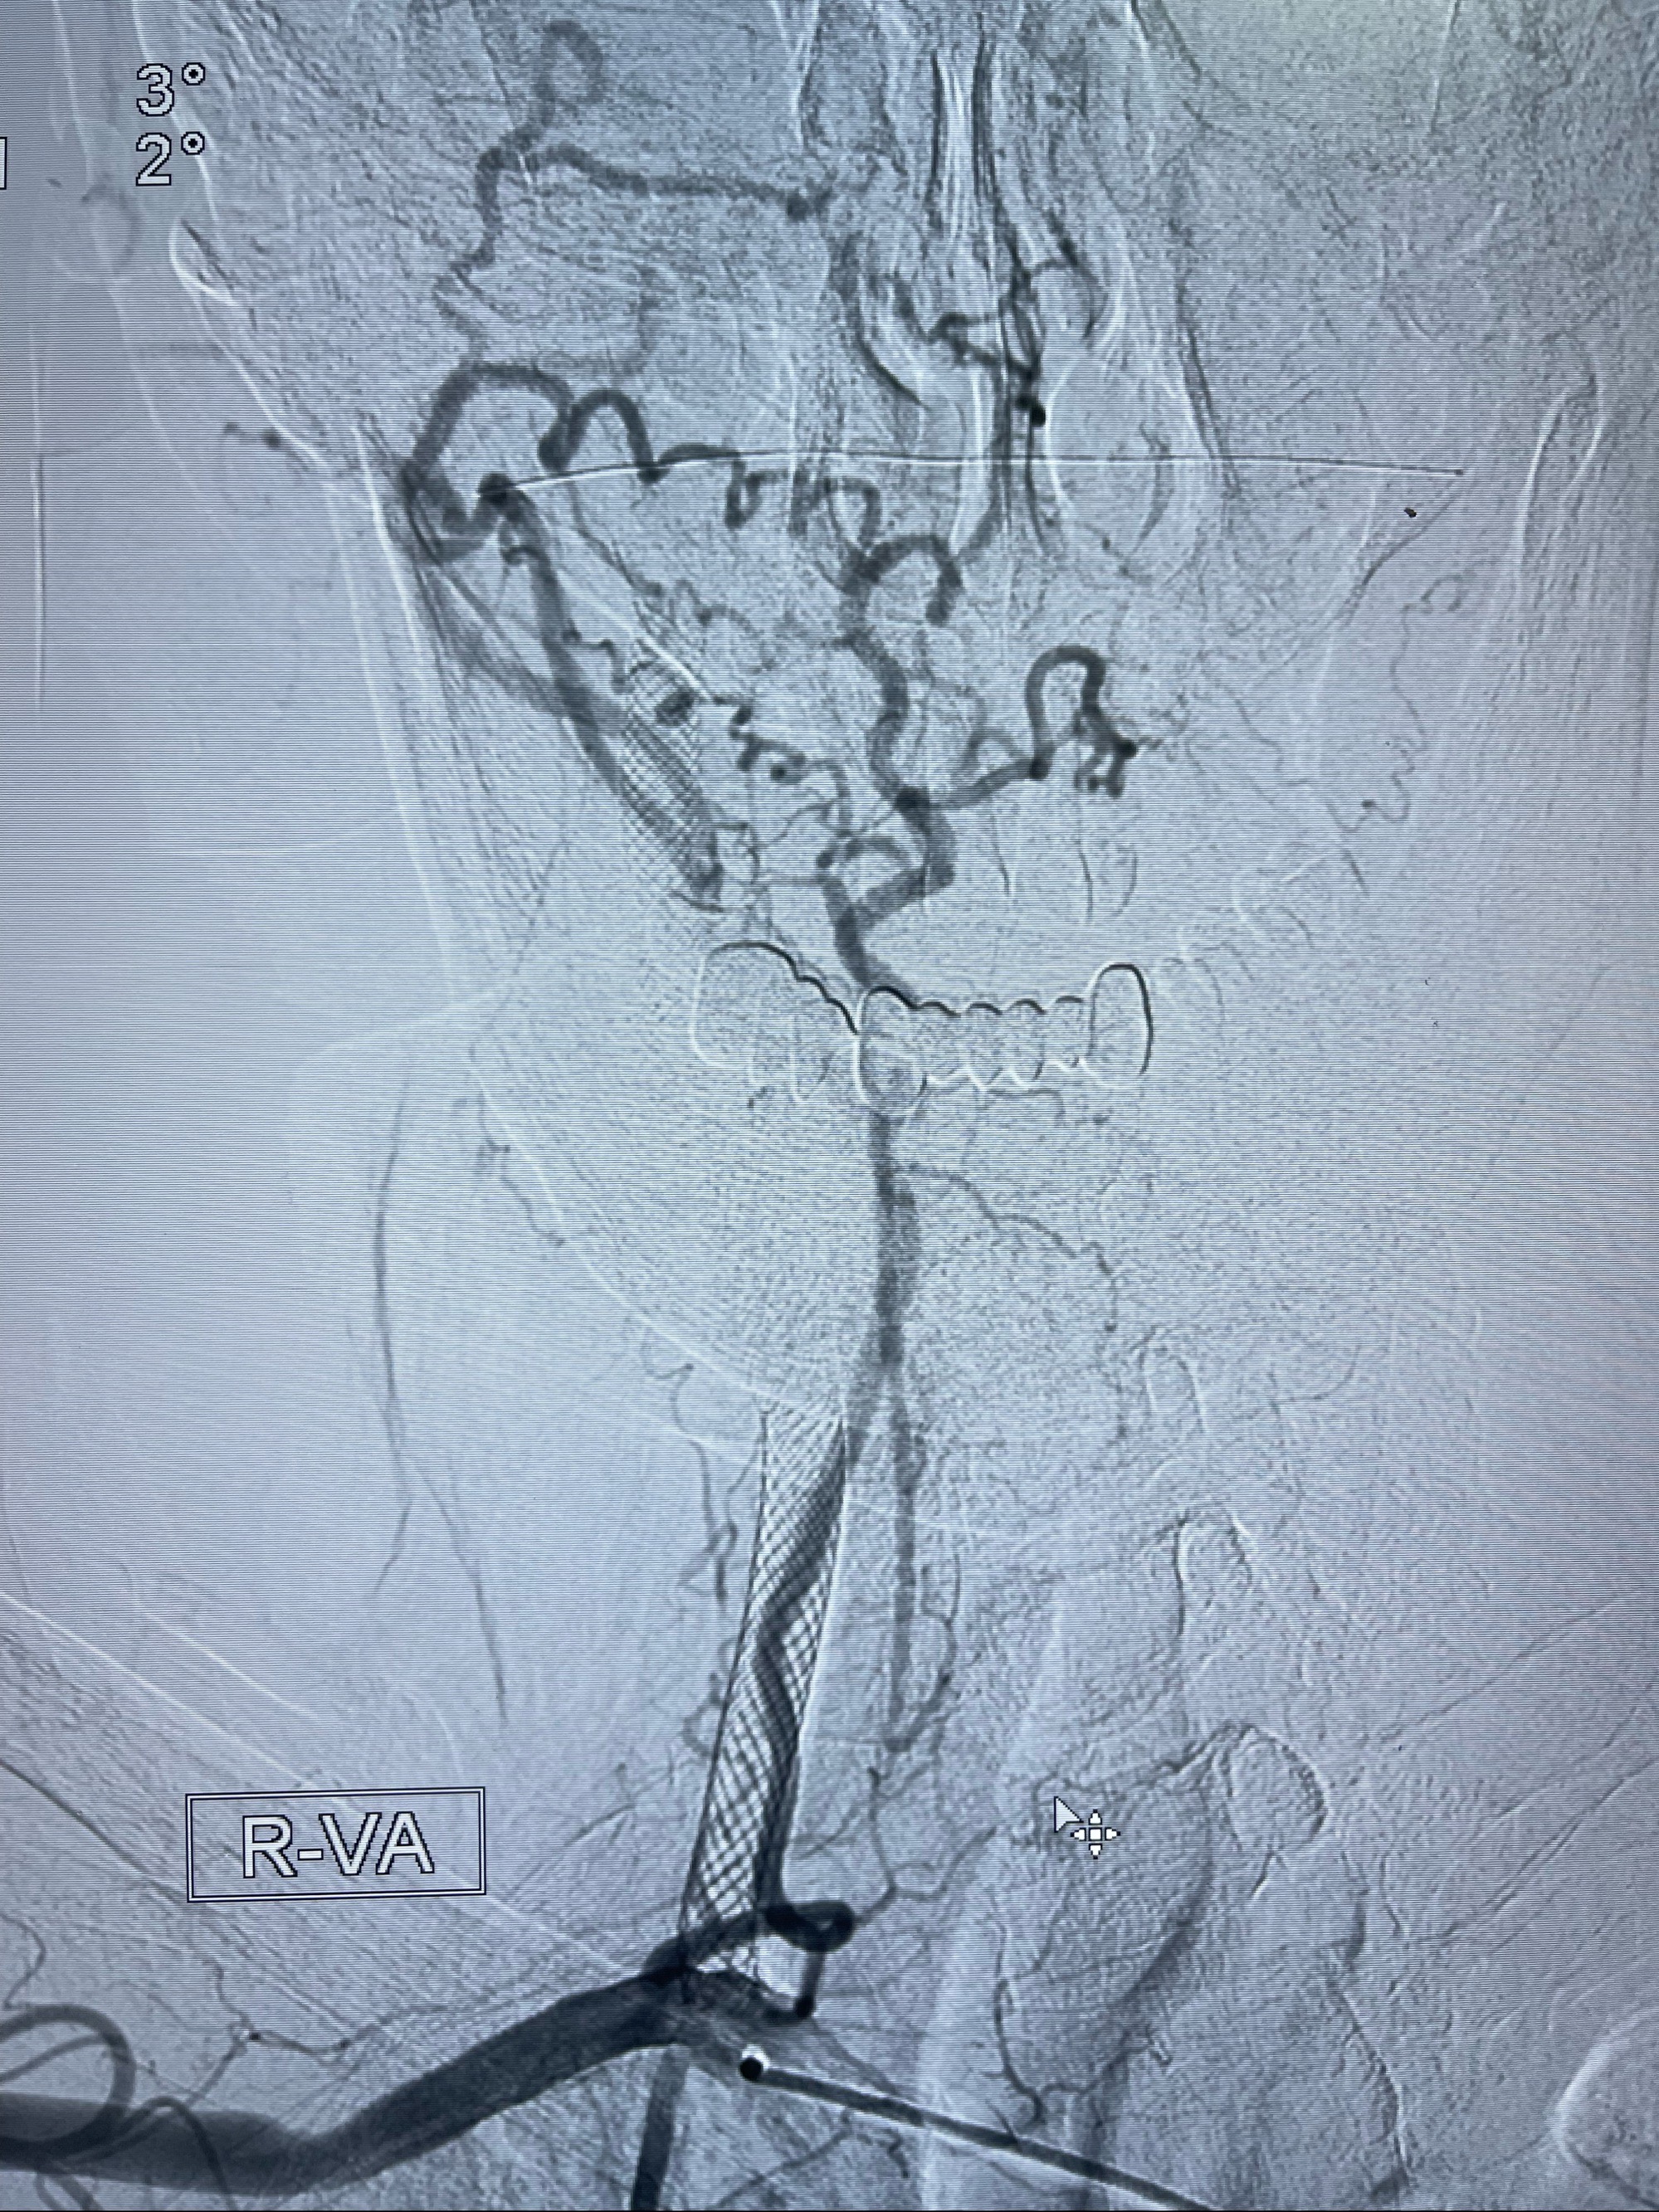

重新行“路径图”,支架导管在微导丝引导下超选择性插入至右侧颈内动脉眼段,4.5-50mmLeo支架释放,远心端位于海绵窦段,近心端位于岩骨段狭窄段以近

即刻造影显示支架贴壁佳

路径图下,5.5-50mmLeo支架导管在微导丝引导下超选择性插入远段Leo支架内

两枚支架部分重叠

多次确认支架位置及打开贴壁情况

支架完全打开,近心端位于原颈动脉支架远心端内